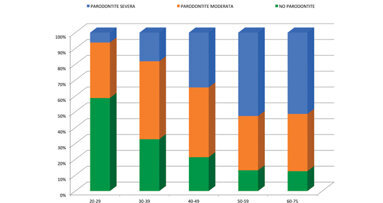

Risultati della prima ricerca epidemiologica in Italia secondo le linee guida dei Centers for Disease Control and Prevention e dell’American Academy ...

Risultati della prima ricerca epidemiologica in Italia secondo le linee guida dei Centers for Disease Control and Prevention e dell’American Academy ...